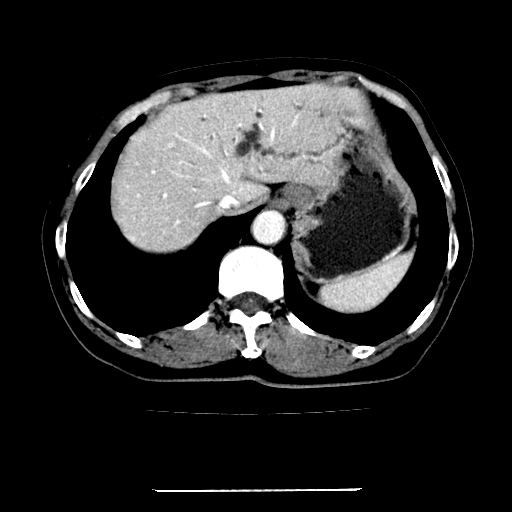

标题: CT22301:女,67岁,上腹部疼痛一周伴皮肤黄染,无发热。 [打印本页]

女,67岁,上腹部疼痛一周伴皮肤黄染,无发热。

左叶肝内胆管结石,并远端肝内胆管扩张。

考虑:肝内胆管结石继发肝内胆管扩张,右肾旋转不良。

肝内外胆管结石并肝内胆管扩张。

建议薄层观察,除外肝门部胆管细胞癌

考虑肝胆管癌;胰头占位?【形态失常,体积增大】

1、肝门高密度影下层面和胰头层面可见轻度胆管扩张,而静脉和延迟期均未见扫描完胰头,不能完全排除胰头占位。2、肝门部高密度影,考虑钙化或结石。

考虑肝门胆管癌伴门脉左支受侵包埋,建议mrcp进一步检查。